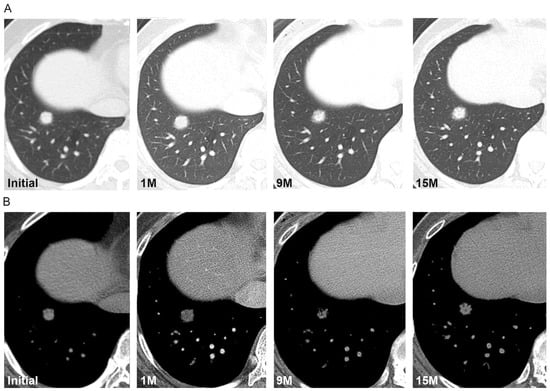

| Change during follow-up period | |

| None | 10 (59) |

| Decrease in size/density or fluctuation in size/shape/density | 3 (18) |

| Increase in size/density | 4 (24) |